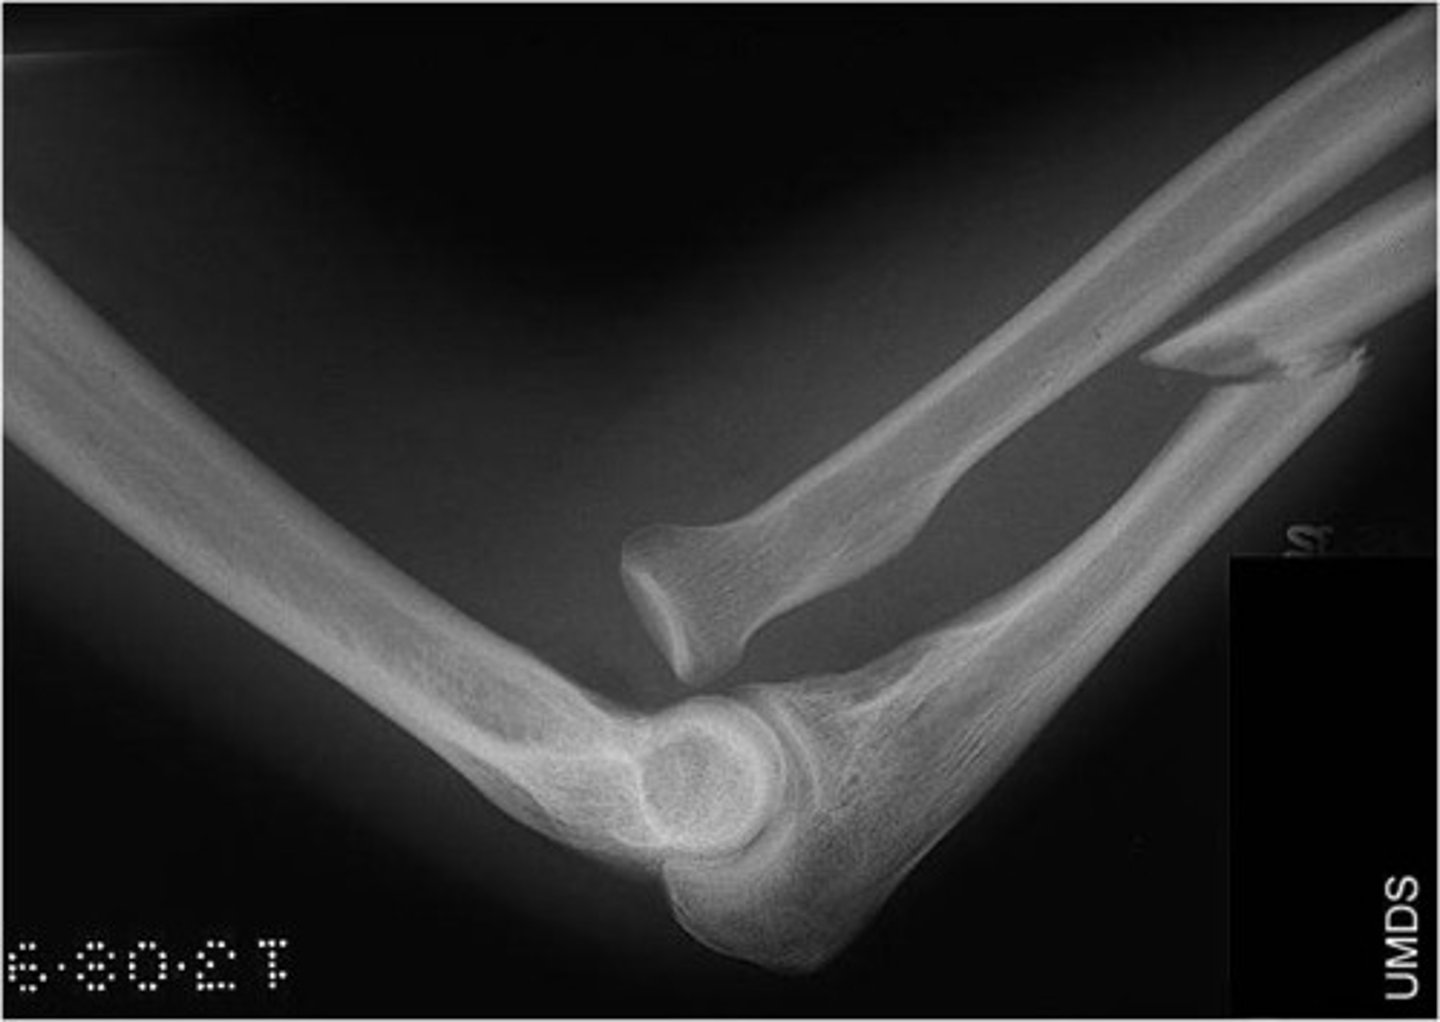

what sign on XR indicates joint effusion?

fat pad sign

if you see fat pad/sail sign on XR, which fracture would you suspect?

occult fx or intra-articular fx

- subtle radial head fx in adults

- supracondylar fx of humerus in children